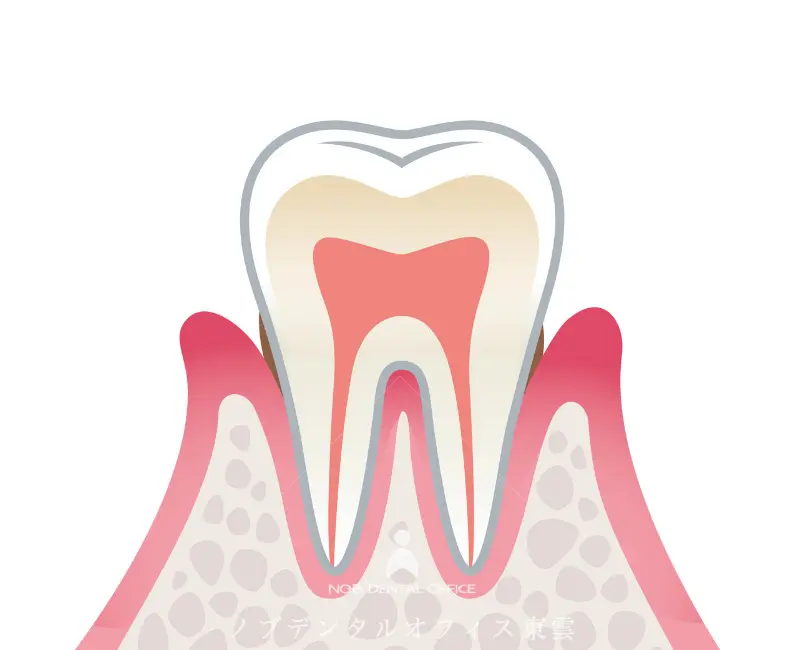

健康な歯ぐき

健康な歯ぐきは引き締まり、ピンク色で、歯にしっかりと付いています。

腫れや出血はなく、歯を支える骨もしっかり保たれています。